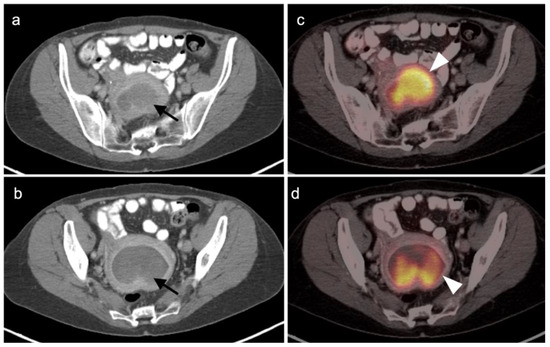

2.4. Cervical Cancer

2.5. Vaginal Cancer

2.6. Vulvar Carcinoma